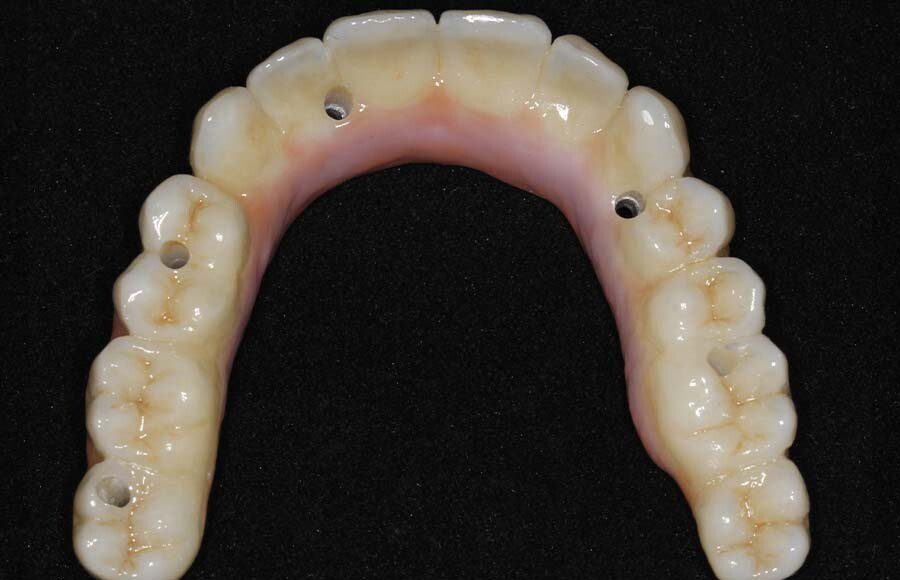

Occlusal (mirror) view of the upper implants. This patient had good bone in these five areas. If the bone was better we would have added a sixth implant.

Tissue-view of the final implant bridge. Note the convex (cleansable) contours. This is a wide departure from “All-on-4” treatment which is virtually uncleansable.